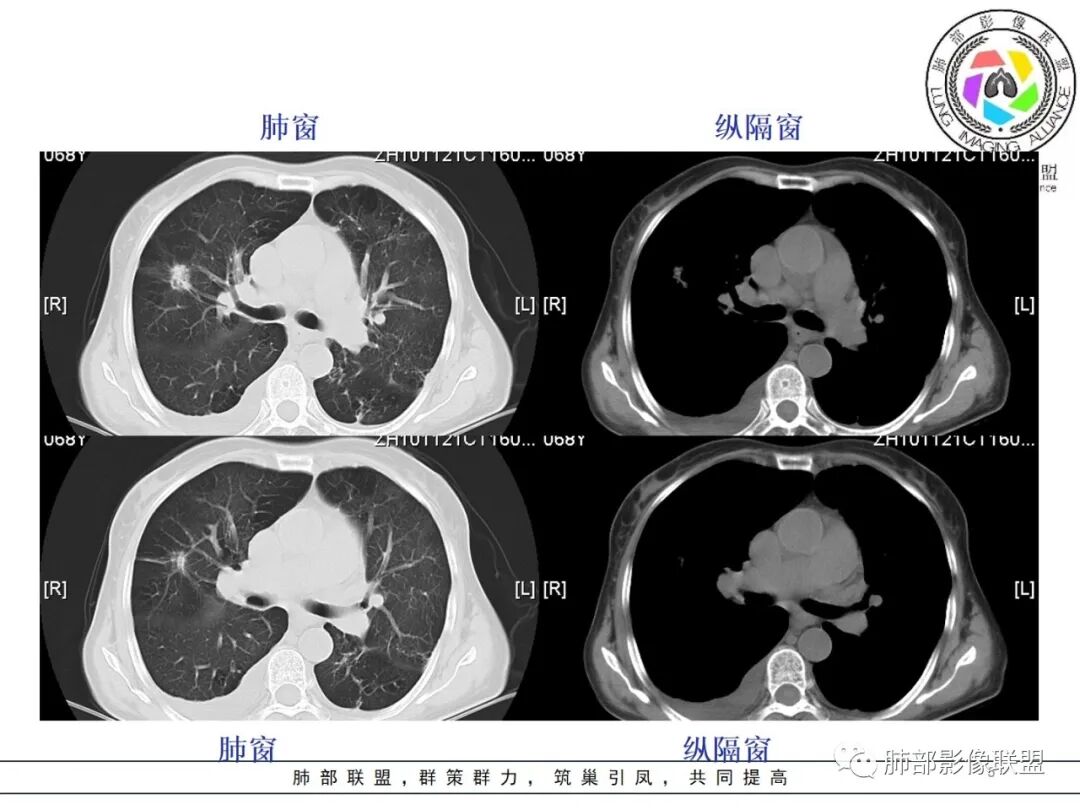

杨丽:

老年女性,肺气肿背景。右肺上叶不规则肿块,局部膨隆,有边界清晰磨玻璃影,细长毛刺,胸膜牵拉,收缩力中等,外朝内生长,后段部分支气管似闭塞,不均匀较明显强化,坏死边界欠清;近八年复查明显增大。考虑腺癌可能性大,鉴别结核。

王开金江津中心医院呼吸科:     老年女性,痰血,右肺新生物,毛刺,分叶,胸膜凹陷,支气管截断,空炮,周围有部分磨玻璃,淋巴结肿大,结合肿瘤标志物升高,考虑肺恶性肿瘤,倾向腺癌。鉴别结核。

红星:    女性68岁,右肺上叶前段结节,将近7年的时间明显长大,表现出分叶毛刺及支气管截断伴胸膜凹陷,增强明显的不均匀强化,纵隔内多发的淋巴结肿大。左肺多发的斑点及条索状间质改变。考虑右肺上叶前段恶性病变,腺癌的可能性大。鉴别诊断结核或炎性肉芽肿。

宇宙:  右肺上叶不规则肿块,较8年前结节明显增大,可见分叶,毛刺,胸膜牵拉,边缘清晰磨玻璃影,上叶后段支气管堵塞,不均匀延迟强化,有坏死,纵隔淋巴结增大,考虑恶性,腺癌,鉴别炎性肉芽肿

孔儿 :   老年女性,右肺上叶前段结节8年复查明显增大,收缩力强,分叶,毛刺,邻近胸膜牵拉,部分支气管截断,周围见边界清晰磨玻璃成分,增强扫描呈不均匀强化,考虑恶性肿瘤,浸润性腺癌可能性大。

刘强:   老年女性,右肺上叶不规则肿块,月牙铲,有收缩,分叶,毛刺,近8年后结节明显增大,边缘清晰磨玻璃影,上叶后段支气管堵塞,不均匀延迟强化,有坏死,纵隔淋巴结增大,考虑恶性,腺癌可能性大

Yishion:   时间跨度虽然大,但原病灶增大,常规需要考虑恶性肿瘤,支气管截断,不符合淋巴瘤,时间太长,说明病灶相对生长过慢,如果是鳞癌,一般破坏力很强,8年时间很难支撑得下来,常规考虑腺癌

蓝天白云:    老年女性,右肺上叶不规则肿块,月牙铲,有收缩,分叶,毛刺,边缘清晰的磨玻璃影,上叶后段支气管截断,胸膜牵拉凹陷,不均匀延迟强化,内见空泡,纵隔淋巴结增大,IAC。所以的恶性征象都有了

丽:    病灶八年明显增大,右肺上叶不规则肿块,边缘毛刺、分叶,胸膜牵拉,并可见清晰磨玻璃密度影,临近支气管截断,增强后不均匀强化,内可见多发低密度,纵膈肿大淋巴结,考虑恶性,常规考虑腺癌

飞鹰行动:   老年女性,右肺上叶前段结节8年复查明显增大,收缩力较强,有分叶,长短毛刺,邻近胸膜受牵拉,部分支气管截断和受牵拉,周围见边界清晰磨玻璃成分,增强扫描呈不均匀强化,内部低密度区可见磨玻璃强化,边缘模糊,考虑恶性肿瘤,腺癌可能性大。鉴别结核,后者强化不明显,支气管牵拉后扩张。

任广国:    病灶发展8年,从混合磨玻璃密度到实性肿块,毛刺分叶明显,胸膜牵拉,(收缩力较强),中等度强化

1、老年女性,肺气肿背景,咯血多年,肿瘤标志物升高。    2、右肺上叶不规则结节影,八年后进行性增大为肿块,边缘深分叶、毛刺、棘状突起、胸膜牵拉,相应支气管壁增厚阻塞;周围局部见边界清楚的磨玻璃影;近胸壁侧见凹陷,整体呈外朝内生长。增强扫描呈不均匀明显强化,其内见坏死区,边界欠清。    3、右侧胸腔积液。纵隔见增大淋巴结。

影像及临床符合肺腺癌的诊断。8年的时间为我们展示这样一个生长过程,还是具有一定程度参考意义的。